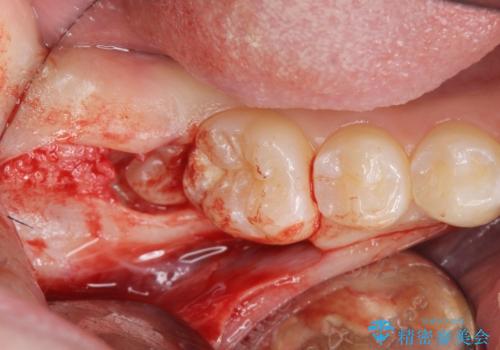

- 右上下親知らずを抜きたいとの事で来院。

レントゲンを確認したとこと完全埋伏歯でした。

CTで神経の位置などを確認し、抜歯術を行いました。

無事抜歯を行うことができました。